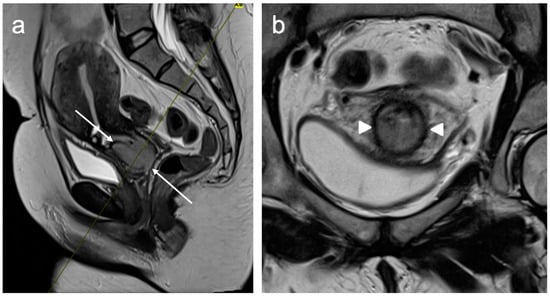

9. Recurrent Cervical Cancer

- Miccò, M.; Lupinelli, M.; Mangialardi, M.; Gui, B.; Manfredi, R. Patterns of Recurrent Disease in Cervical Cancer. J. Pers. Med. 2022, 12, 755. [Google Scholar] [CrossRef] [PubMed]